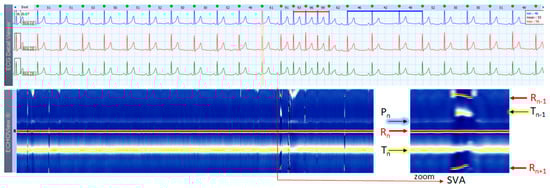

3.2. NSR, SVES, VES Cases

This section interprets together 3-lead Holter ECG strips and the corresponding ECHOView images (ECG lead 1) of two patients in sinus rhythm with frequent supraventricular (Figure 4) and ventricular extrasystoles (Figure 5). Detailed interpretation of the zoomed ECHOView color map in the area of interest around one extrasystole is presented in the caption of the figures. In general, SVES and VES can be easily recognized as occasional narrow vertical lines of a different color from the background color map presented by NSR. In the zoomed ECHOView images, we can identify important SVES and VES differences vs. sinus rhythm beats, such as the early non-sinus ventricular depolarization visible as a red dot in the blue horizontal area between T-waves and P-waves (Figure 4 and Figure 5); typically for VES morphological alterations—the wider R-waves, the black spots with ST-segment depression and the T-wave electric axis inversion (Figure 5). Despite ECHOView being useful for the localization of vertical lines of extrasystoles at a glance, the ECG trace is mandatory to verify their type.

4.3. ECHOView: Summary of the Principles of Imaging

ECHOView modality discloses clearly in a color-coded pattern the presence and morphology of different ECG waves in sequential beat intervals. Thanks to the highly distinctive color map (black-blue-white-orange-red), the ECG waves can be easily discerned and their alignment to the central R-peak can be tracked in long duration ECHOView pages (mean duration of 24.5 min per page). This is especially important for the traditionally difficult recognition of the P-wave, which in all example cases is visible as a blue-white horizontal trace above R-peaks when present in NSR (Figure 4, Figure 5, Figure 9, Figure 10 and Figure 11), SINT (Figure 6, Figure 7 and Figure 8) and PSVT (Figure 10, Figure 11 and Figure 12). Similarly, a series of vertically displaced white traces are recognized for the F-waves in AFL (Figure 15 and Figure 16). On the contrary, a white horizontal P-wave trace is missing in NSVT (Figure 17) and AF (Figure 13, Figure 14 and Figure 16), where f-waves are discerned as randomly located light spots. The presence or absence of the P-wave in SVES and VES beats is difficult to be recognized in compressed ECHOView pages unless the area of the ectopic beat is zoomed as in Figure 4 and Figure 5 (right). Nevertheless, the identification of SVES/VES is possible by observations of the red dots (R-peak) and yellow/orange dots (T-peak) visible as occasional events in the blue horizontal area between Tn−1 and Pn (Figure 4 and Figure 5). Additionally, VES are associated with a change in the QRST waveform compared to NSR beats, which is recognized on the ECHOView color map as a contrasting color change, e.g., in Figure 5 from blue to black (during the negative T-wave of VES). Whereas the inspection of such color changes for single VES beats requires a zoomed ECHOView image (Figure 5), the recognition of NSVT episodes including multiple VES beats seems easier in the compressed ECHOView page (Figure 17). However, our observations of NSVT are limited because these are rare events in our Holter ECG population, observed in only 3 patients with short rushes ≤ 11 beats.